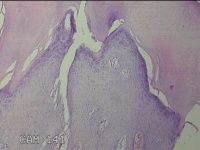

左拇指结节

性别

男

年龄

42岁

临床诊断

皮下结节

一般病史

发现左拇指结节8年余。

标本名称

大体所见

灰白粉红色组织1.3x0.8x0.3cm一块,表面带梭形皮肤1.3x1.1cm,皮下见结节0.8x0.5cm一个,切开结节呈实性,切面灰白粉红色,质中。

良性病变。